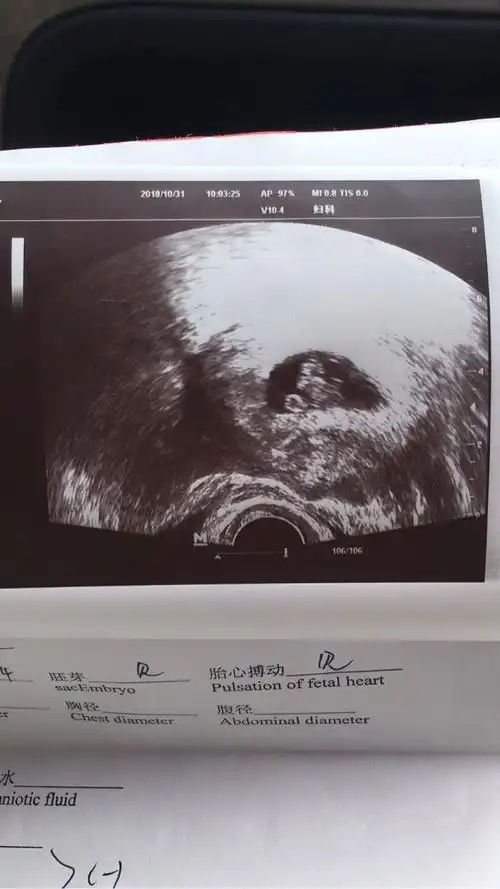

胎心胎芽